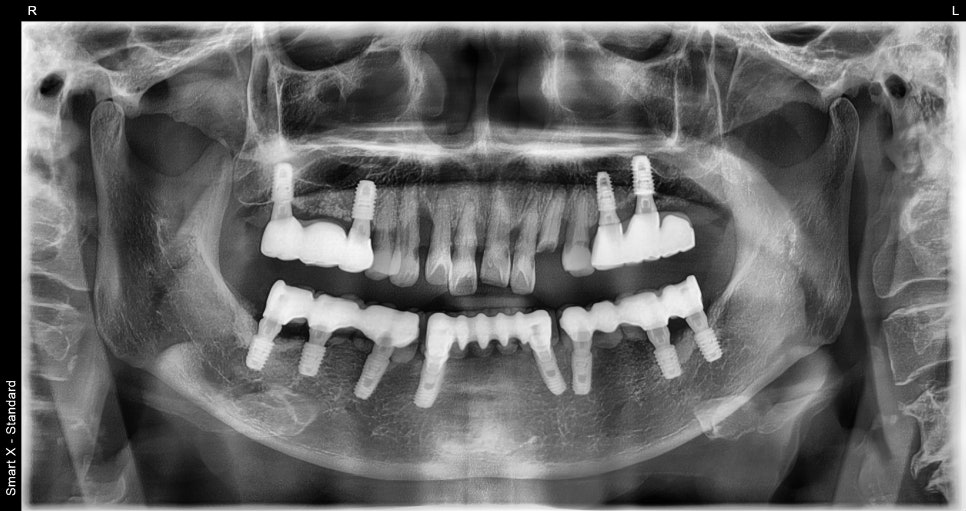

초진내원당시

이번 환자분은 65세 여성으로

위 앞니가 여러 개 상실된 상태로 내원하셨습니다.

발치와 동시에 진행된 임플란트 식립

이번 케이스에서는

손상된 앞니를 발치한 후

임플란트 식립이 동시에 진행되었습니다.

✔ 전치부 다수 임플란트 식립

✔ 골유도재생술(GBR) 진행

✔ 동종골 이식 병행

앞니는 뼈가 얇기 때문에

뼈이식

이 함께 진행되는 경우가 많습니다.